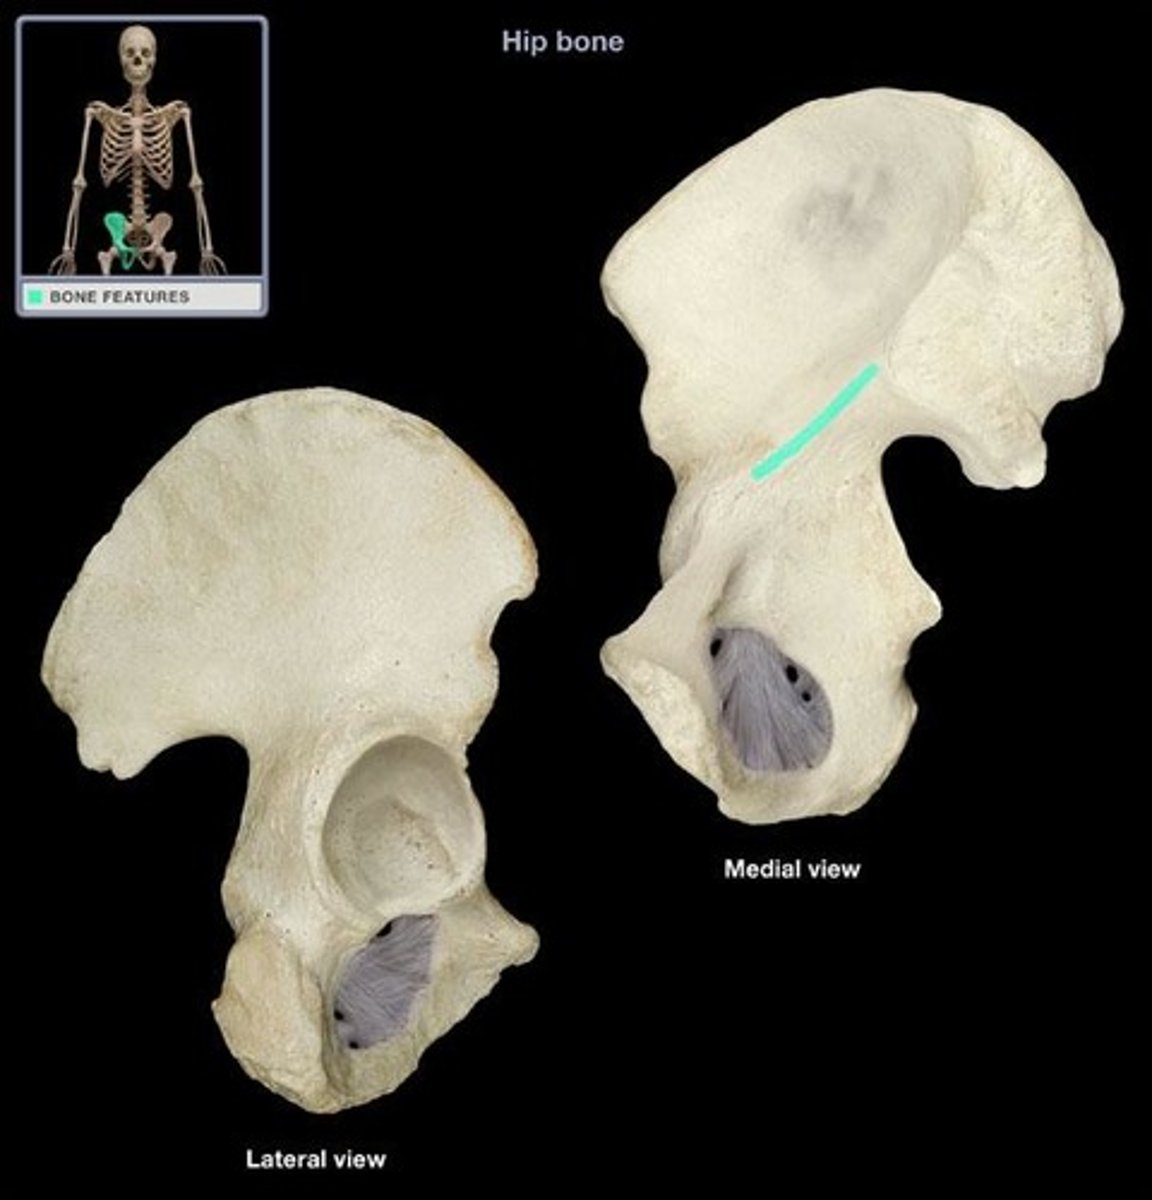

ox coxae

hip bones

3 bones fused together, anteriorly connected at the pubic symphysis and posteriorly at the sacrum

ilium

weight bearing during sitting

pubis

The medial anterior portion of the pelvis

ischium

the lower, posterior portions of the pelvis

iliac crest

upper margin of iliac bones

posterior superior iliac spine

the sharp posterior end of the iliac crest

posterior inferior iliac spine (PIIS)

a bony projection located inferior to the posterior superior iliac spine

anterior superior iliac spine

origin of sartorius

anterior inferior iliac spine (AIIS)

origin of rectus femoris

iliac fossa

The broad, slightly concave inner surface of the ilium.

Acetabulum

large socket in the pelvic bone for the head of the femur

acetabular notch

deep notch in the inferior part of the brim

greater sciatic notch

allows blood vessels and the large sciatic nerve to pass from the pelvis posteriorly into the thigh

ischial tuberosity

receives the weight of the body when sitting

body of ischium

Makes up all of the ischium superior to the tuberosity

ramus of ischium

joins the inferior ramus of the pubis anteriorly

obturator foramen

opening in hip bone formed by the pubic and ischial rami

body of pubis

origin of adductor longus

arcuate line

a ridge of bone that runs inferiorly and anteriorly from the auricular surface, forms pelvic brim

iliopubic eminence

marks the point of union of the ilium and the pubis just lateral to the arcuate line

pubic tubercle

An attachment point for the inguinal ligament.

superior ramus of pubis

origin of pectineus

inferior ramus of pubis

origin of adductor brevis